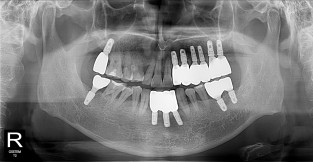

무치악

치료기간 : 2023-02-21 ~ 2023-10-21

1. 상기 x-ray 이미지 모두 동일한 해당 의료기관에서 진료한 환자입니다.

2. 상기 x-ray 이미지 모두 동일 인물의 것입니다.

3. 치료 전 이미지는 2023-02-21에 촬영했으며, 치료 후 이미지는 2023-10-21에 촬영하였습니다.

4. 상기 x-ray 이미지 모두 동일 조건에서 환자분의 동의를 받아촬영되었습니다.

* 임플란트 시술은 환자분의 상태(고혈압, 당뇨 등)에 따라 부작용이 있을 수 있으니, 반드시 전문의와 상담이 필요합니다.

* 임플란트 수술 부작용

: 수술 후 출혈, 교합, 통증, 붓기, 염증 등의 문제점이 발생할 수 있습니다.)